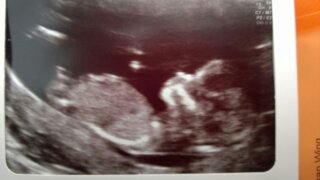

Getting to know myself through the eyes of my child